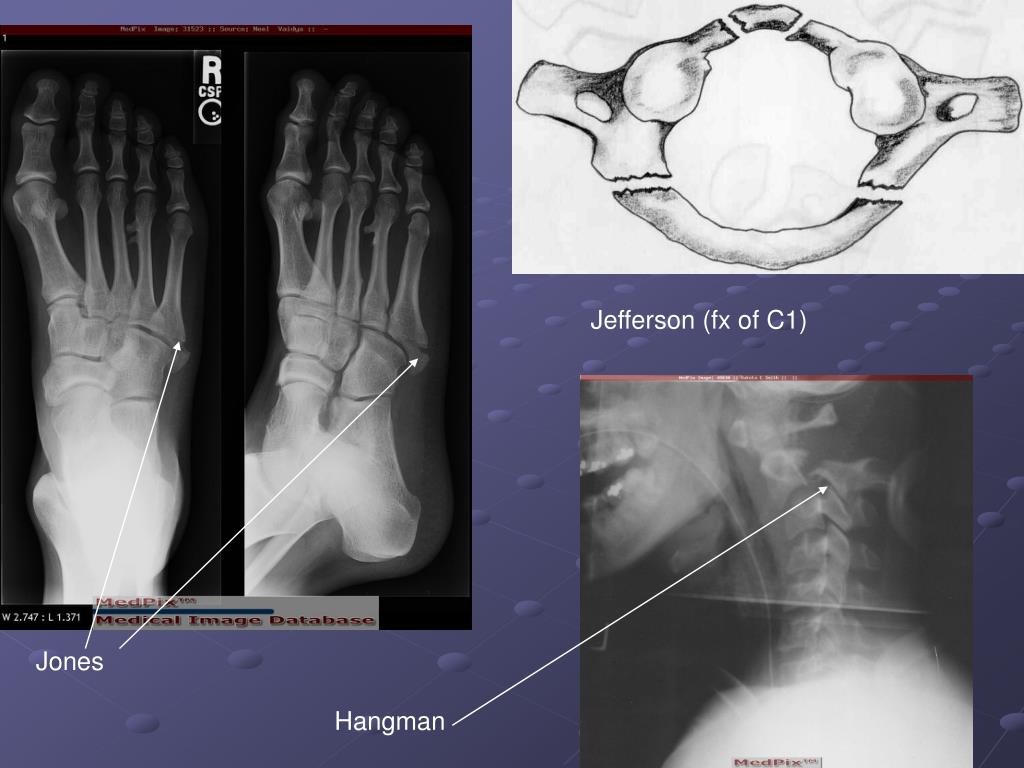

12. Lisfranc- fx in which one/many metatarsal bones are dislocated from tarsal bones. Jones- fx of the base of the 5th metatarsal of foot Jefferson- fx of Cervical 1 Hangman- fx of Cervical 2 Seat Belt- fx of the body of the Lumbar vertebrae; normally due to trauma Blowout- fx to the floor of the orbit (maxillary and zygoma bones) Tripod- fx to the floor and lateral aspect of the orbit Fractures

18. Jefferson (fx of C1) Jones Hangman